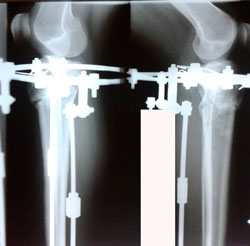

Исходник - 38 лет.

Дата операции 23.03.2020

Вложения

image-01-04-20-11-29-5.jpg

image-01-04-20-11-29-3.jpg